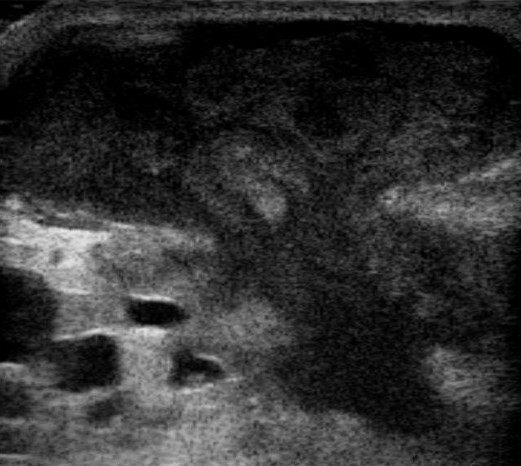

농양은 조직, 장기 또는 제한된 공간에 고름이 모여 형성된 국소적인 집합체이며, 화농성 막으로 덮여 있다.[25] 초음파 검사는 농양 진단에 도움이 될 수 있다.[26]

초음파 검사는 농양 진단에 도움이 될 수 있다.[26]

농양은 조직, 장기 또는 제한된 공간에 묻혀 있는 화농성 염증 조직인 고름이 모여 형성된 국소적인 집합체이며, 화농성 막으로 덮여 있다.[25] 초음파 검사는 진단에 도움이 될 수 있다.[26]농양은 새로 형성된 해부학적 공간이 아닌 기존의 해부학적 공간에 고름이 축적되는 농흉과 감별해야 한다.[29] 유사한 증상을 유발할 수 있는 다른 질환으로는 봉와직염, 피지 낭종, 괴사성 근막염 등이 있다.[4] 봉와직염은 일반적으로 발적 반응을 동반하지만, 화농성 배액은 나타나지 않는다.[20]